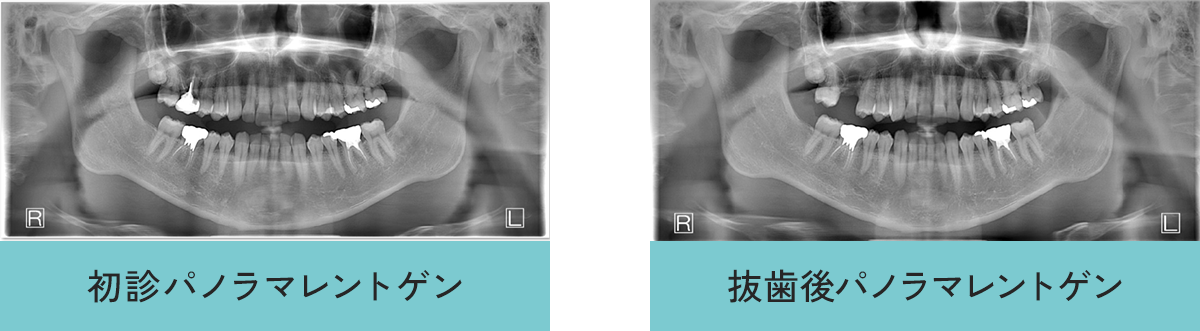

インプラント症例

- 年齢・性別

- 30代男性

- 主訴

- 右上奥が痛む

- 診断名

- 右上奥歯(第1大臼歯)重度う蝕(虫歯)のため保存不可能

- 治療内容

- 重度虫歯の右上奥歯を、抜歯後、骨ができてからインプラント治療を行う。

- 治療期間

- 約1年

- 治療費用

- 総額558000円(税込)

・インプラント治療498000円 【埋入(インプラント入れること)、上部構造 被せ物)含む】

・ソケットリフト50000円 - リスク